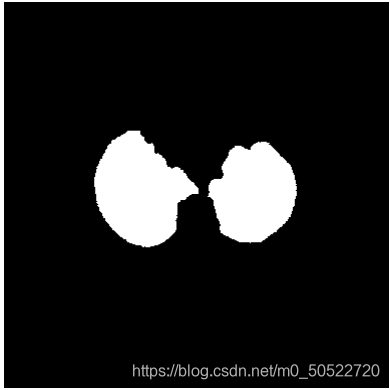

(6)消除气管

由上图可看出,虽然步骤5已经将肺质提取出来了,但是由于肺部中存在气管,所以在二值化以后会看到气管依然存在在二值图中,此时如果我们想得到没有气管的单独肺质时就需要对上图进行区域消除处理,定义一个适中的面积值,计算各连通区域的面积,由于肺质的连通面积较大,此时就使用定义的面积阈值,将小于此面积阈值的部分消除。即可得到单独的肺质如下图所示。